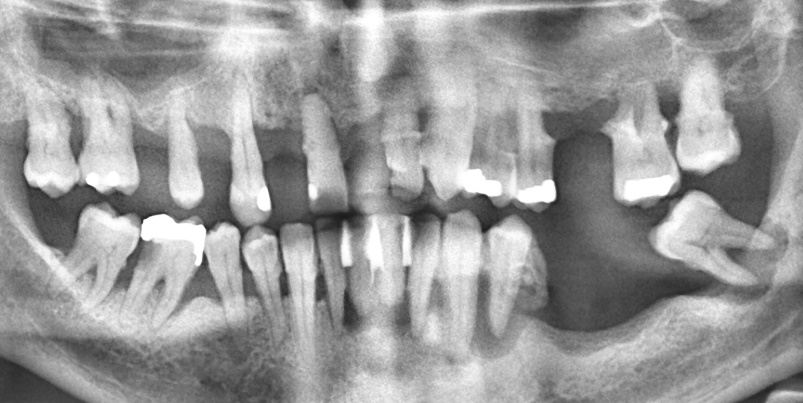

Irregularly attending patient who requested dental implants. The patient had generalised Stage IV periodontitis, caries in tooth 46 and gross calculus on all teeth and was high risk for peri-implant disease and implant failure.